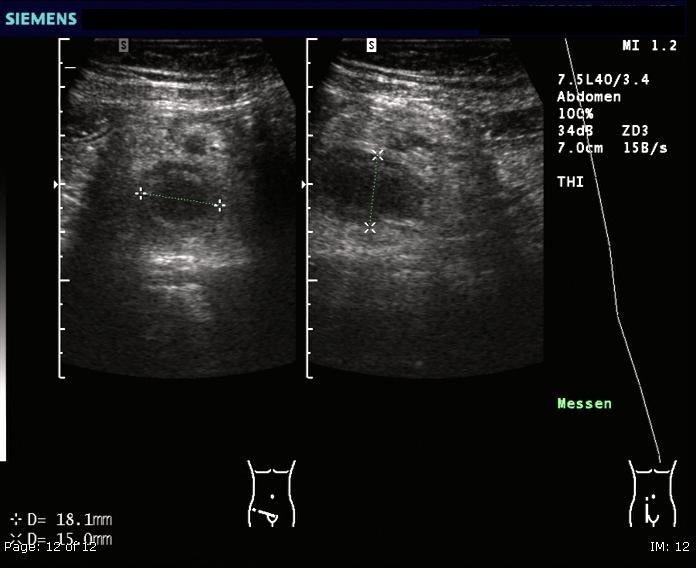

Ultrasound is useful in females with suspected pelvic organ pathology, while CT scans are commonly used in the US but less so in the UK due to radiation concerns.

Ultrasound examination may show evidence of lumenal obstruction and thickening of the appendiceal wall as shown below